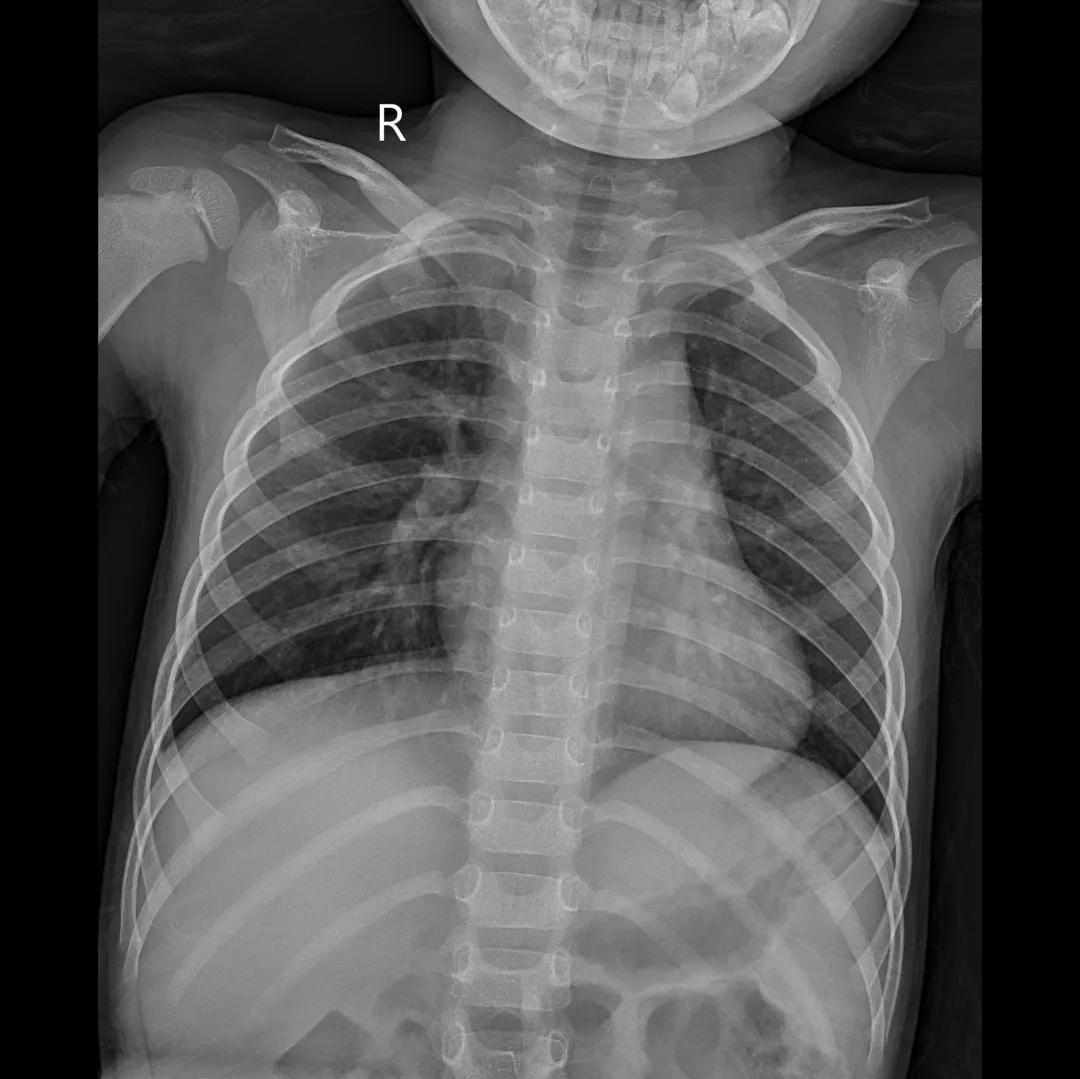

最后来看看“飞燕”的临床成像:

滑动查看更多图片

据了解,移动DR“飞燕”目前已在国内外多家医院服役,在这次全球新冠肺炎疫情期间,安健公司的上百台移动DR奔赴疫区,助力新冠肺炎患者的影像诊断和筛查。继国内疫情得到缓解之后,安健又积极联合各方力量,向老挝、泰国、巴基斯坦、摩洛哥、菲律宾、缅甸、乌兹别克、意大利等疫情国家提供移动DR。这些设备正从国内出发,陆续交付至国外客户手中,用于全球抗疫……